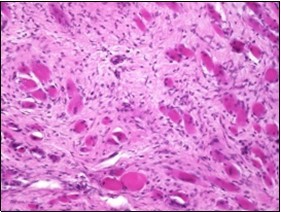

On microscopy, a collagen- rich, minimally cellular, fibrotic soft tissue nodule is exemplified which simulates a scar or conventional fibroma. The neoplasm is comprised of uniform, plump, fibroblastic or myo-fibroblastic cells encompassed in a collagen-rich stroma with infiltration and entrapment of skeletal myocytes 5, 6. Cogent histological examination depicts replacement of muscle fibres and muscle mass with fascicles of fibrous tissue comprised of mature fibroblastic cells, thereby conferring fibrosis 6. Figure 1, Figure 2, Figure 3, Figure 4, Figure 5, Figure 6, Figure 7, Figure 8.

Figure 1.Fibromatosis colli depicting bundles of fibroblasts and myo-fibroblasts intermixed with a collagenous stroma and entrapped myocytes 9.

Figure 2.Fibromatosis colli demonstrating fascicles of fibroblasts and myo-fibroblasts within an abundant collagenous stroma and several mature myocytes 10.

Figure 3.Fibromatosis colli depicting fascicles of fibroblasts and myo-fibroblasts admixed with a collagenous stroma and extravasation of numerous red blood cells 10.